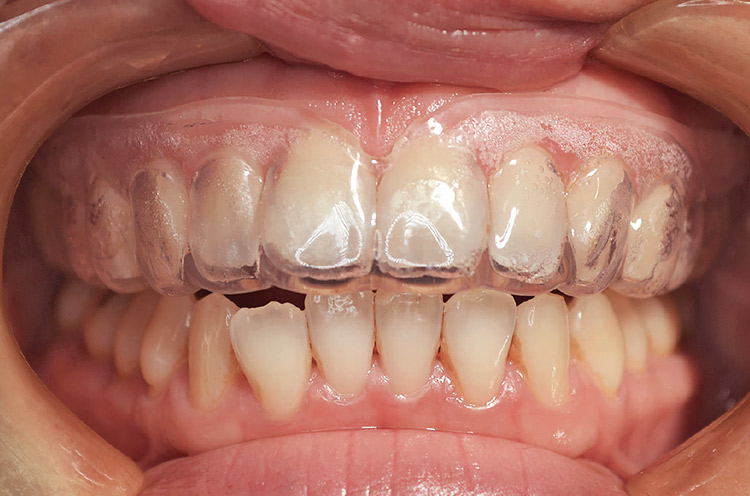

研磨においても、シート材の温度をできる限り上昇させないように注意する。特に艶出しに専用バーナーを用いる場合には、素早い操作を心がける。マウスガードフィニッシャーなどの薬液を用いても、ある程度の艶出しは可能である。研磨後のマウスガードの状態(図19)と口腔内への装着状態(図20)を示す。

図20 口腔内に装着したマウスガード(正面観)。